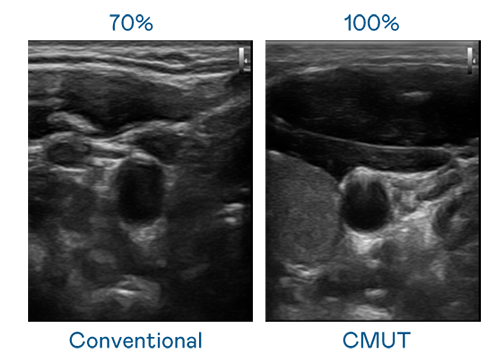

CMUT 技术是一种用电容式微机电元件来产生超音波讯号的技术。与传统 PZT 压电式技术相比,CMUT 频宽增加 30%,更宽频的超音波讯号让影像解析度大幅提升,是实现高影像品质医疗超音波扫描、促进精准医疗发展的关键技术。

大频宽带来超清晰影像

超音波影像的解析度高低,首先取决于探头能发出的讯号频宽。东升国际链接入口 CMUT 可提供高清晰的超音波讯号,提供高频宽、高灵敏度、影像纹理细节更高的超音波影像,协助医护人员缩短影像判读时间及利用精准的医疗影像进行诊断。